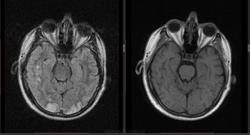

Мужчина 1964 г.р. Жалобы на нарушение памяти, снижение зрения и кратковременную потерю сознания, температура нормальная.

Я думаю что это может быть какой нибудь васкулит, либо Posterior Reversible Encephalopathy Syndrome, о чем можно думать в данном случае?

eto pres

Я представлял синдром с более выраженным изменением сигнала от белого вещества и меньшим - коры.